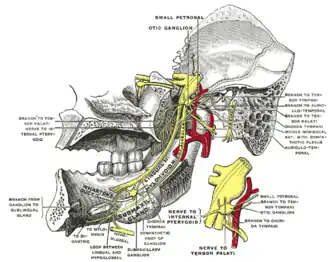

Mandibular division of trifacial nerve, seen from the middle line. The small figure is an enlarged view of the otic ganglion. ("Wharton's duct" labeled in lower left.) | |

The submandibular duct arises from deep part of submandibular gland, a salivary gland. It begins by numerous branches from the superficial surface of the gland, and runs forward between the mylohyoid, hyoglossus, and genioglossus muscles. It then passes between the sublingual gland and the genioglossus and opens by a narrow opening on the summit of a small papilla (the "sublingual caruncle") at the side of the frenulum of the tongue. It lies superior to lingual and hypoglossal nerves.

The submandibular duct was initially described by the English anatomist Thomas Wharton ( 1614-73) and is sometimes referred to by his name.[6]